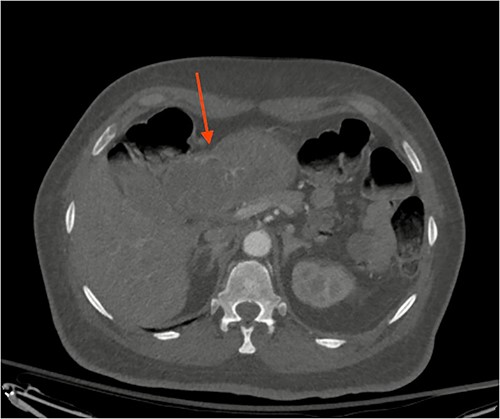

After a few days, the patient was found to have a large volume of melenic stool. A CT angiogram of the chest, abdomen and pelvis was done, revealing a mass in the antrum and pylorus of the stomach with a portion of the stomach pulled into it, consistent with gastroduodenal intussusception without any active extravasation. Repeat EGD showed a large, fungating, pedunculated mass with no bleeding and no stigmata of recent bleeding in the gastric body (Figs. 3 and4) and confirmed gastroduodenal intussusception. The intussusception spontaneously reduced while attempting to push passed the mass. The mass was too large to resect endoscopically. Given these new findings, the family agreed to surgical intervention. An exploratory laparotomy was made, and the patient underwent partial gastrectomy, distal antrectomy and Billroth II procedure. The resected large gastric body mass within the mid gastric body and two nodes were sent for frozen section and immunohistochemical analysis. The pathology report confirmed the mass as a GIST, spindle cell type with no significant nuclear atypia or mitosis, arising from muscularis propria, without mucosal invasion and R0 margins. The neoplastic cells stained positive for CD117 (KIT), CD34 and Desmin (focally). The tumor was T3N0M0 with a low mitotic rate, histologic grade G1 and was deemed low risk (3.6%). The patient was discharged to a subacute rehab with an uneventful recovery.